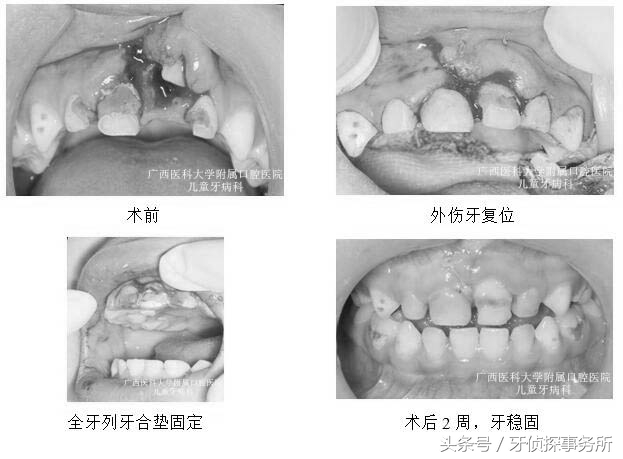

1、部分脱位

碰撞后乳牙在外力的作用下向外或向内倾斜移位后部分脱出牙槽窝时,可将外伤牙恢复到原位后结扎固定,一般预后较好,但日后有可能发生牙髓坏死,根尖感染或牙槽脓肿。如果接近替牙期或者乳牙牙根已吸收1/2以上者可以考虑拔除该颗松动乳牙。